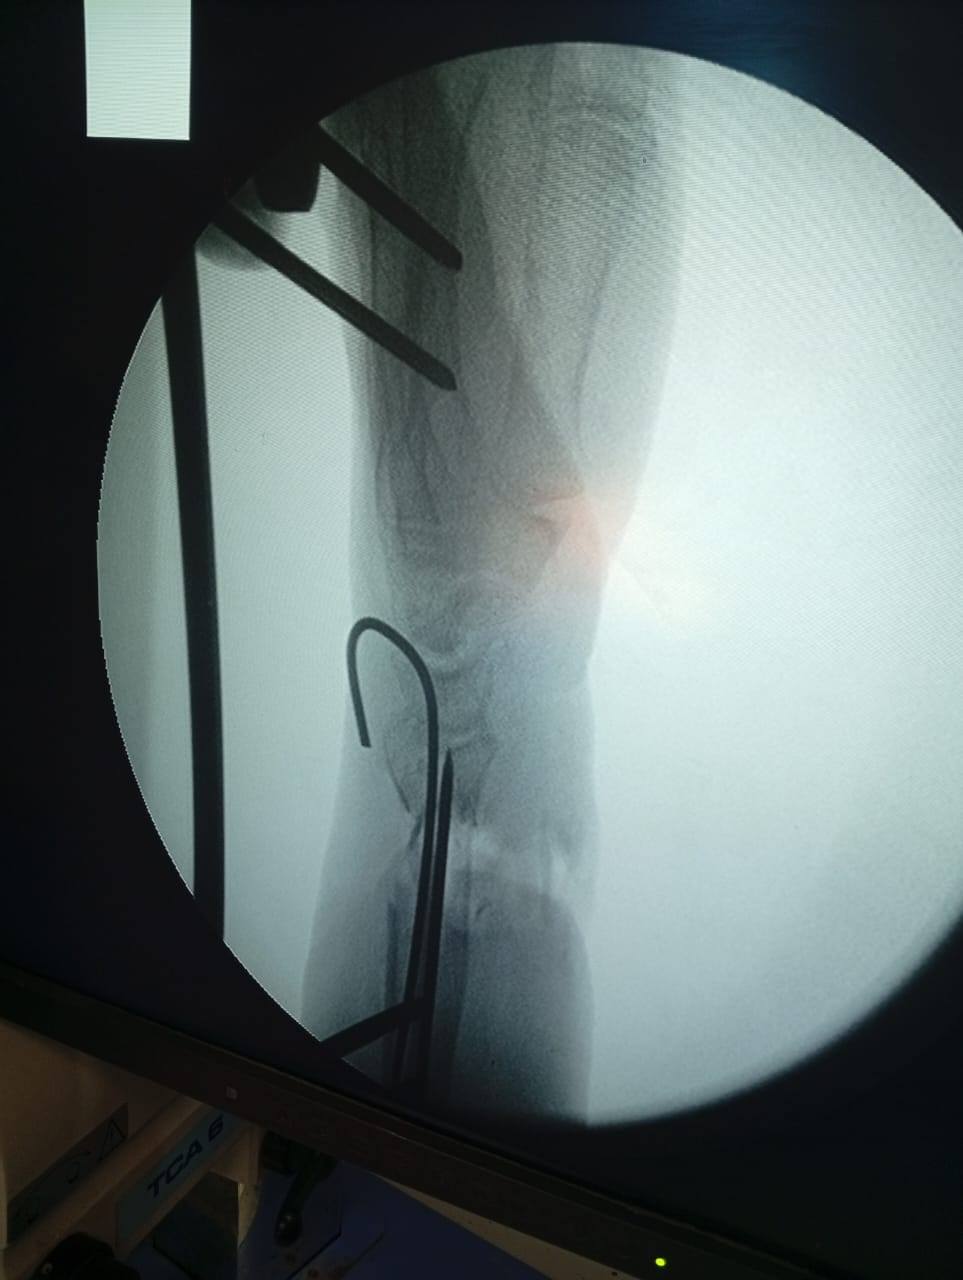

صرحت الدكتورة نيفين شعبان وكيل وزارة الصحة بالفيوم بان مستشفى الفيوم العام بقيادة الدكتور محمد عبد الله استقبلت حالة تُعد من أدق الحالات الجراحية، سيدة تبلغ من العمر 65 عامًا حضرت إلي المستشفى بعد سقوط من ارتفاع، تعاني من تهتك شديد بالجلد وقطع بالأعصاب والأوتار في منطقة الرسغ وتأثر شديد بالدورة الدموية لليد نتيجة كسر مضاعف بعظام الساعد.

بدأ التدخل الجراحي للحالة بتعاون كامل بين اطباء العظام و جراحات التجميل، حيث قام فريق جراحة العظام بتثبيت الكسر المضاعف بدقة عالية.

ثم جاء الدور لـ قسم جراحة التجميل الذي أجرى جراحة ميكروسكوبية دقيقة شملت إصلاح الأعصاب المصابة وإعادة توصيل الأوتار وتحسين الدورة الدموية للرسغ واليد، وذلك بهدف الحفاظ على وظيفة اليد واستعادتها قدر الإمكان.